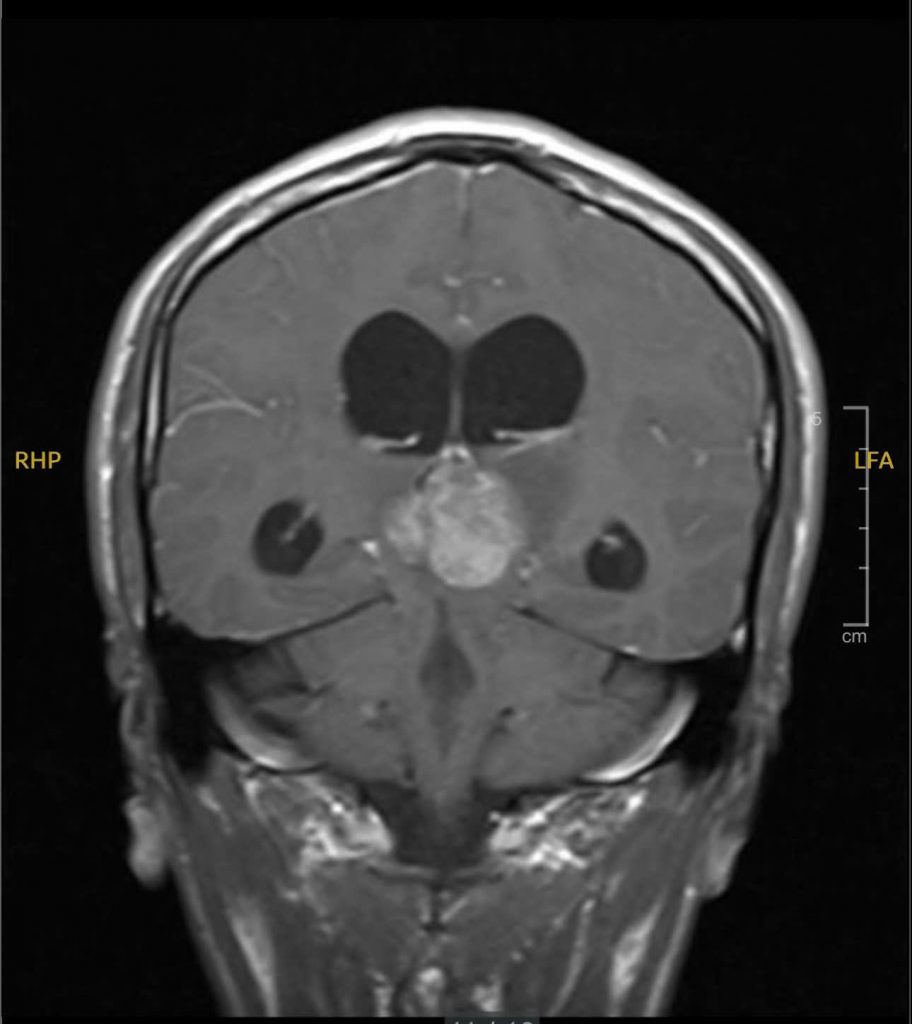

Tại đây, em được chỉ định chụp MRI não thì phát hiện có khối u vùng tuyến tùng – một dạng khối u nằm sâu giữa não, có thể gây chèn ép và cản trở đường lưu thông dịch não tủy. Đây chính là nguyên nhân khiến áp lực nội sọ tăng lên, gây ra những triệu chứng nặng nề mà em trải qua.

Hình ảnh MRI khối u vùng tuyến tùng